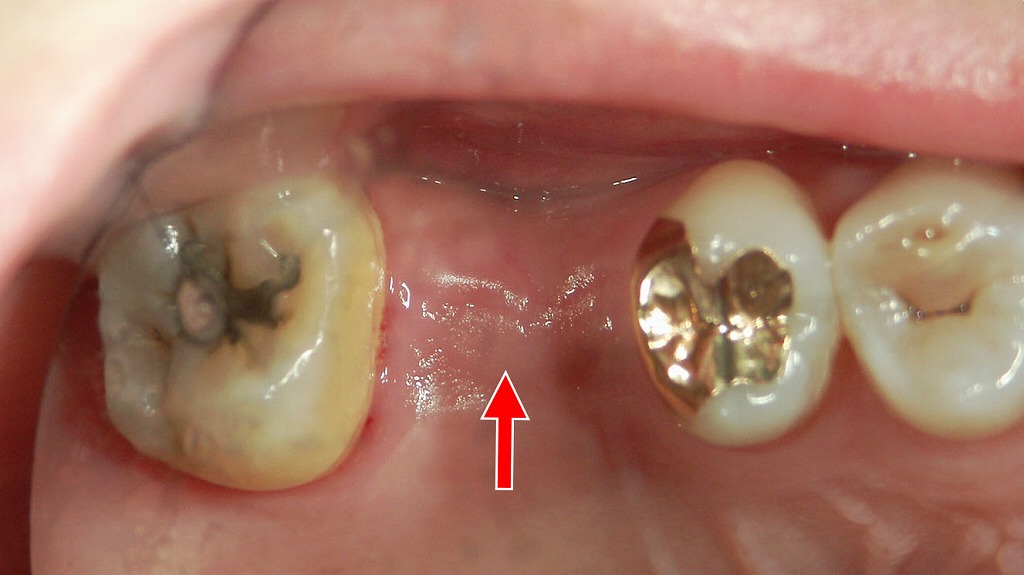

- 7.4. 🔍 左右の下あごに乳歯が残存 第二小臼歯の先天欠損症例

- 7.4.1. ① 両側の下顎:第二乳臼歯の残存(矢印付近)

- 7.4.2. ② 第二小臼歯の先天欠損

- 7.4.3. ③ 咬合や将来への影響

① 両側の下顎:第二乳臼歯の残存(矢印付近)

- 赤い矢印で示されている位置に 乳歯(第二乳臼歯)が残ったまま になっています。

- 通常、第二乳臼歯は12歳前後で抜け、下から第二小臼歯が生えてきます。

- 本症例では、その 永久歯の芽(歯胚)が存在せず、乳歯が自然脱落しない状態 です。

- 乳歯の根はやや短く、加齢とともに吸収していく可能性がありますが、現在は保持されています。